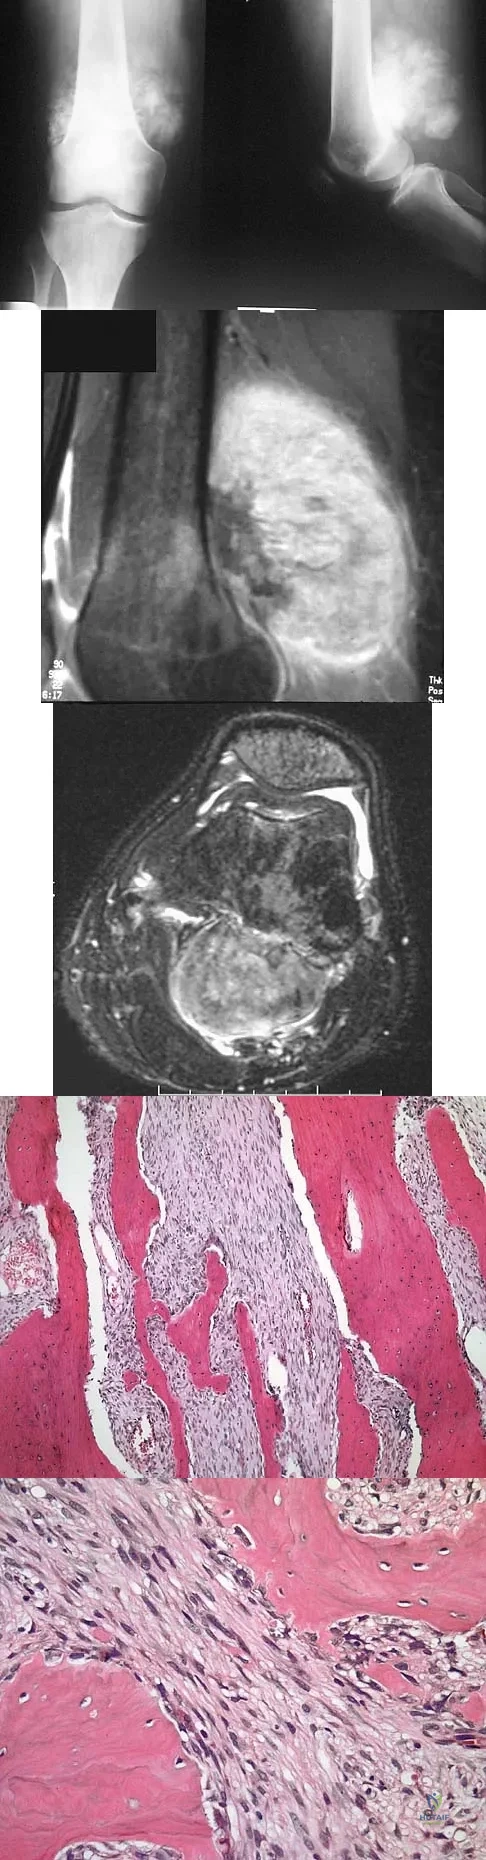

An 18-year-old boy has had pain in the right knee for the past 6 months. Examination reveals some fullness behind the knee but no significant palpable soft-tissue mass. There is no effusion, and he has full knee range of motion. The remainder of the examination is unremarkable. A radiograph and MRI scans are shown in Figures 33a through 33c, and biopsy specimens are shown in Figures 33d and 33e. What is the most likely diagnosis?

Explanation